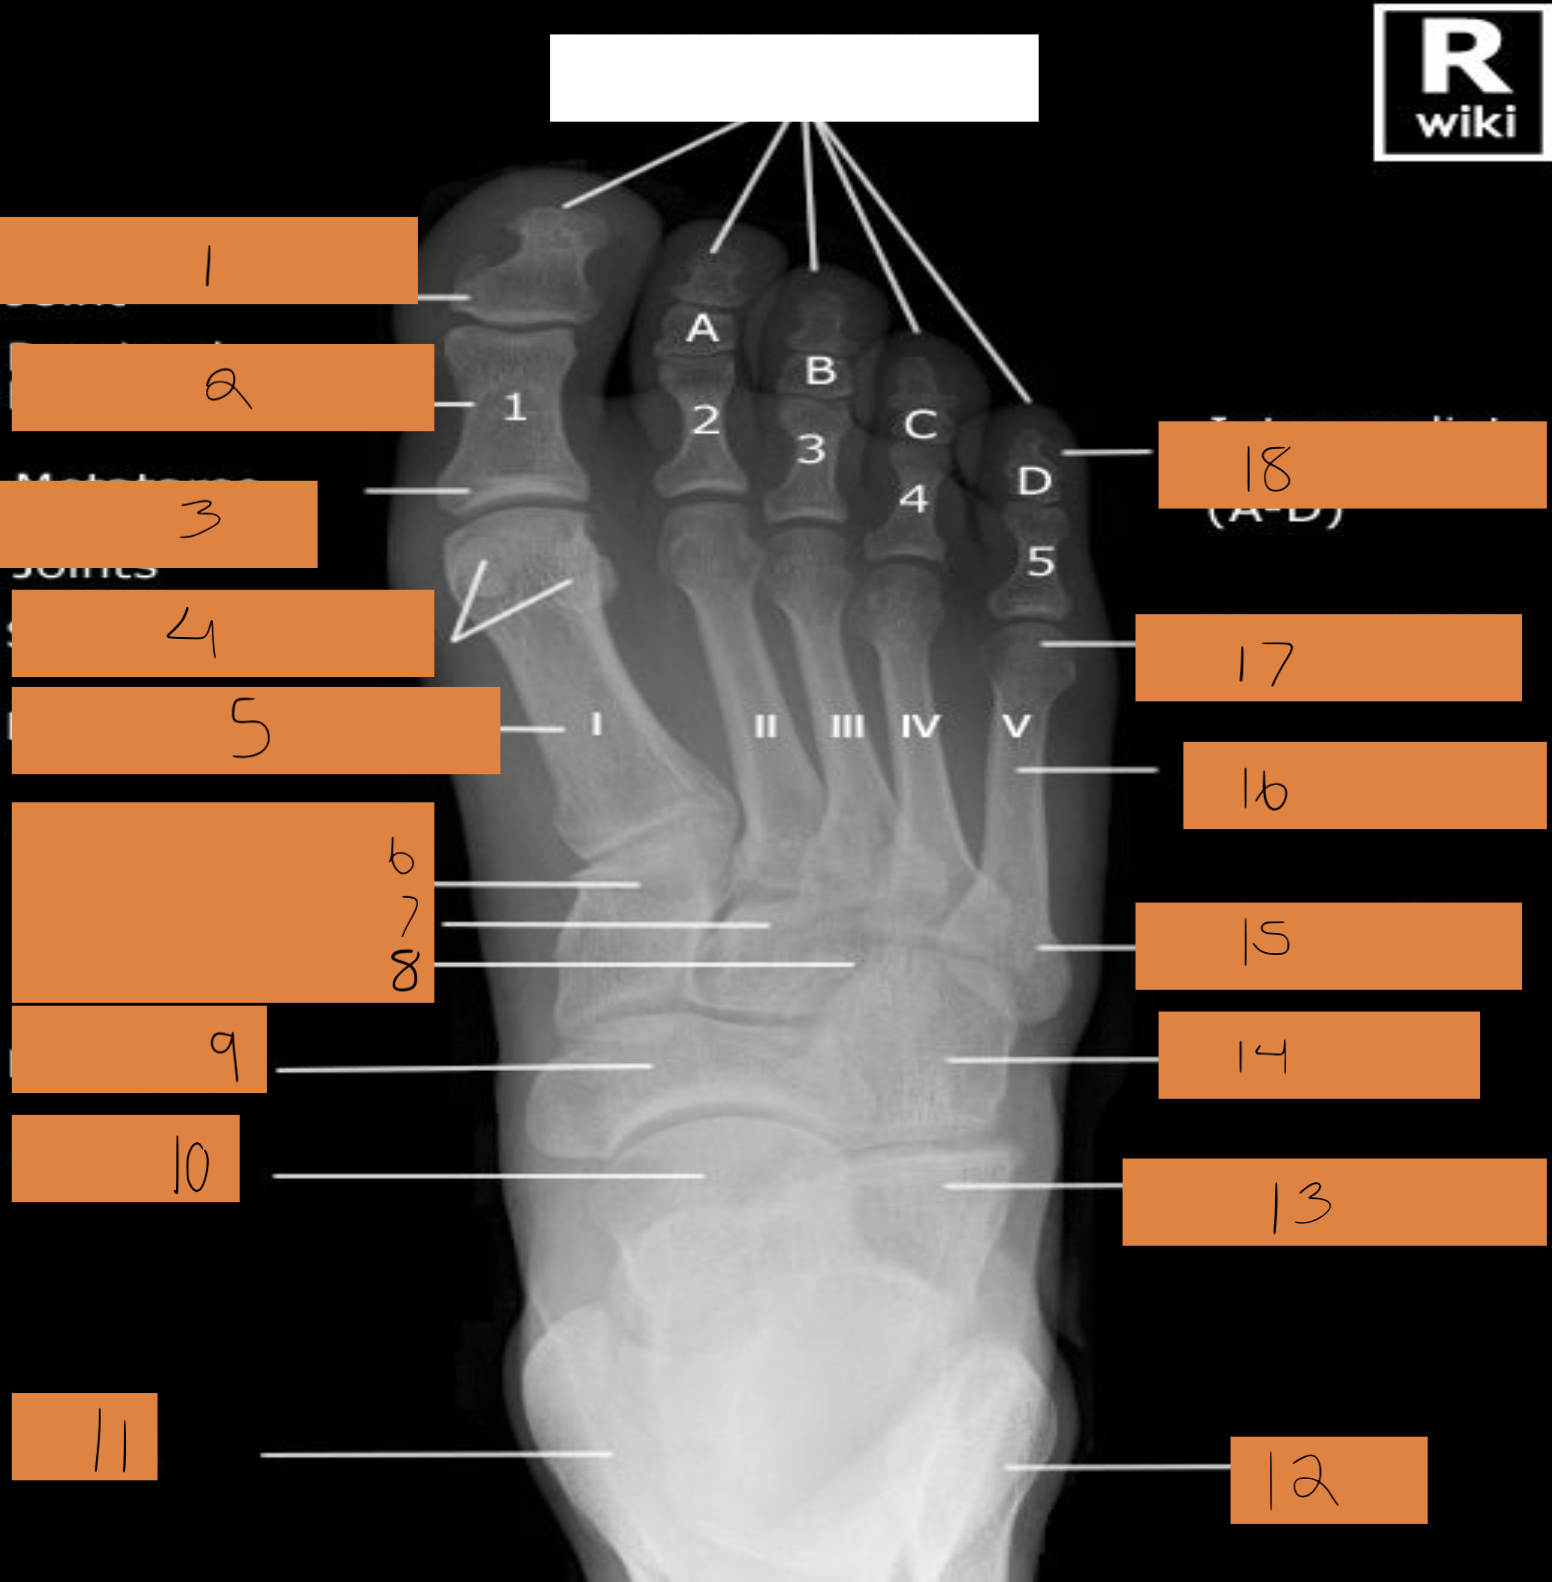

1

interphalangeal joint

2

proximal phalanges 1-5

3

metatarsophalangeal joints

4

sesamoid bones

5

first metatarsals

6

medial cuneiform

7

intermediate cuneiform

8

lateral cuneiform

9

navicular

10

talus

11

tibia

12

fibula

13

calcaneum

14

cuboid

15

base of 5th metatarsal

16

shaft of 5th metatarsal

17

head of 5th metatarsal

18

intermediate phalanges a-d